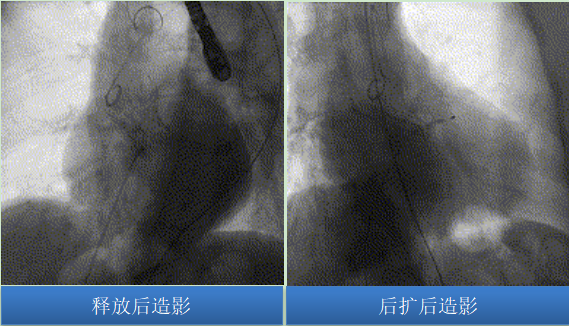

瓣膜釋放后流入端形態(tài)稍受限伴少中量反流,予以22mm球囊后擴(kuò)張瓣膜形態(tài)、位置良好,峰值壓差10mmHg,冠脈血流灌注正常,弓部造影未見異常。

圖片

術(shù)前左室收縮壓:165mmHg,升主動(dòng)脈收縮壓 112mmHg,主動(dòng)脈瓣跨瓣壓差53mmHg;術(shù)后左室收縮壓:145mmHg,升主動(dòng)脈收縮壓 136mmHg,術(shù)后壓差僅9mmHg,左室升主動(dòng)脈跨瓣壓差基本消失。

術(shù)后復(fù)查患者瓣膜功能良好、位置形態(tài)好、無(wú)瓣周漏、無(wú)傳導(dǎo)阻滯。在心血管內(nèi)科醫(yī)護(hù)團(tuán)隊(duì)的精心治療和護(hù)理下,患者恢復(fù)良好,癥狀得到明顯改善,已于近日順利出院!